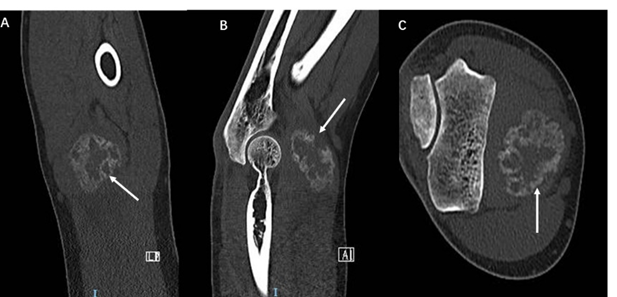

A low-attenuation soft-tissue mass with associated calcifications, typically the peripheral rim becomes increasingly calcified and the central lucent zone is isodense to adjacent brachial muscles. AP view CT showed “popcorn” calcification in soft tissue with radiolucent center and sagittal plane CT revealed the “popcorn” calcification is not from adjacent bones. The axial view CT demonstrated clearly that the calcification mass anterior to distal humerus in brachial muscles (Figure 4). The MRI appearance follows the isointense to hypointense to skeletal muscle on T1-weighted sequences. T2-weighted sequences will appear hyperintense to surrounding muscles. The peripheral low signal intensity can be seen (Figure 5).

Figure 4: A low-attenuation soft-tissue mass with associated calcifications, typically the peripheral rim becomes increasingly calcified and the central lucent zone is typically isodense to adjacent brachial muscles. AP view CT showed “popcorn” calcification in soft tissue with radiolucent center (an arrow in A) and sagittal plane CT revealed the “popcorn” calcification is not from adjacent bone (arrow in B). The axial view CT demonstrated clearly that the calcification mass anterior to distal humerus in brachial muscle (arrow in C).